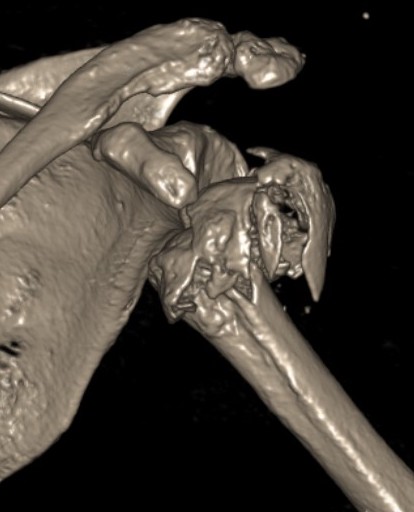

Four part

Avascular necrosis (AVN)

In most fractures, arcuate artery is disrupted, but head survives

- posterior circumflex artery is sufficient

- risk increases with amount of displacement

- 4 part fracture 30%

- 3 part fracture 15%

Hertel et al J Should Elbow Surg 2004

- two criteria to predict ischaemia / 97% predictive if both factors present

- metaphyseal head extension < 8 mm

- medial hinge displaced > 2mm